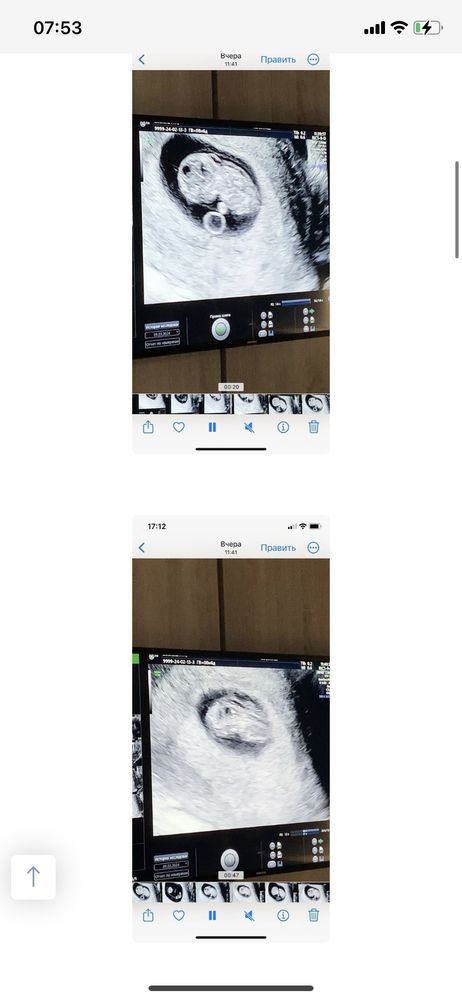

Девочки, доброе утро.. Приложу описание своей ситуации по узи в 9 -то неделек (первые пять фото). Ходила на узи в 9,5 недель (шестое фото) Всё таки есть расширение воротникового пространства? Хожу в платную клинику с самого начала беременности. Попросила её измерить все таки, она померила, но там, где маленькое воротниковое пространство и сказала 1,5, но можно было замерить в другом месте, где оно больше. Вроде в конце она померила большой замер и ничего не сказала мне, а я обратила на это внимание 😢 Я её спросила несколько раз, она сказала, что все хорошо, но мне кажется, что она меня так просто успокаивает..